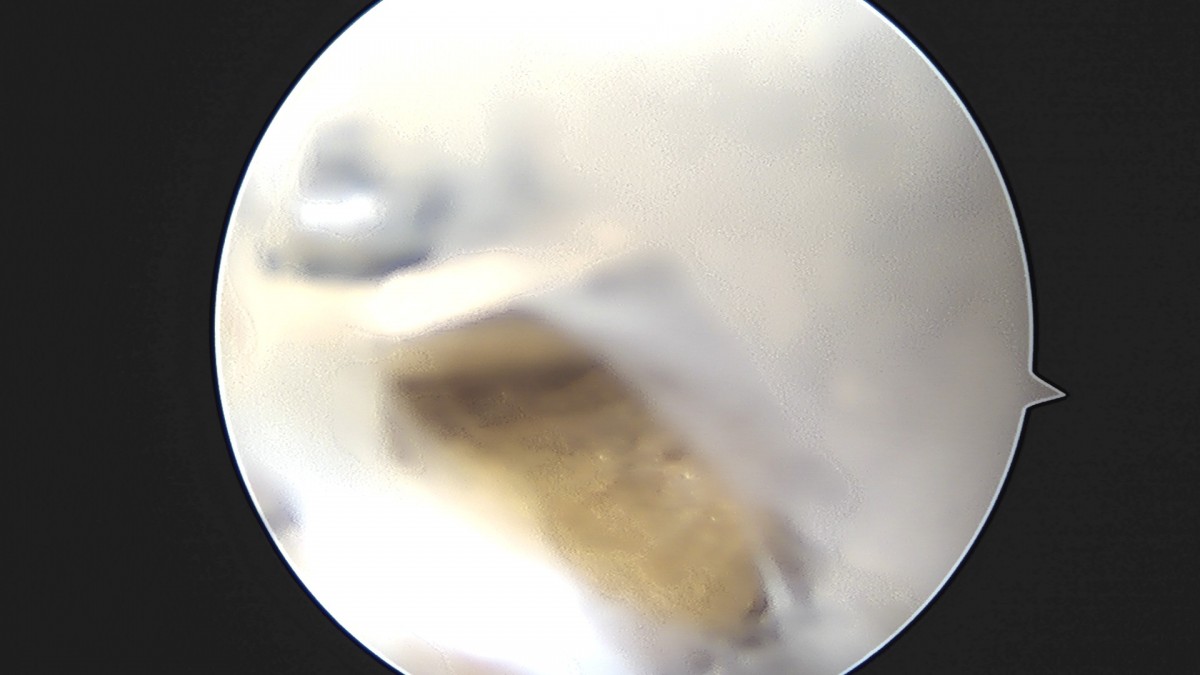

이재상원장님 어깨 견봉하 감압술 이승O 환자

작성자 최고관리자 댓글 0건 조회 806회 작성일 25-09-16 15:26